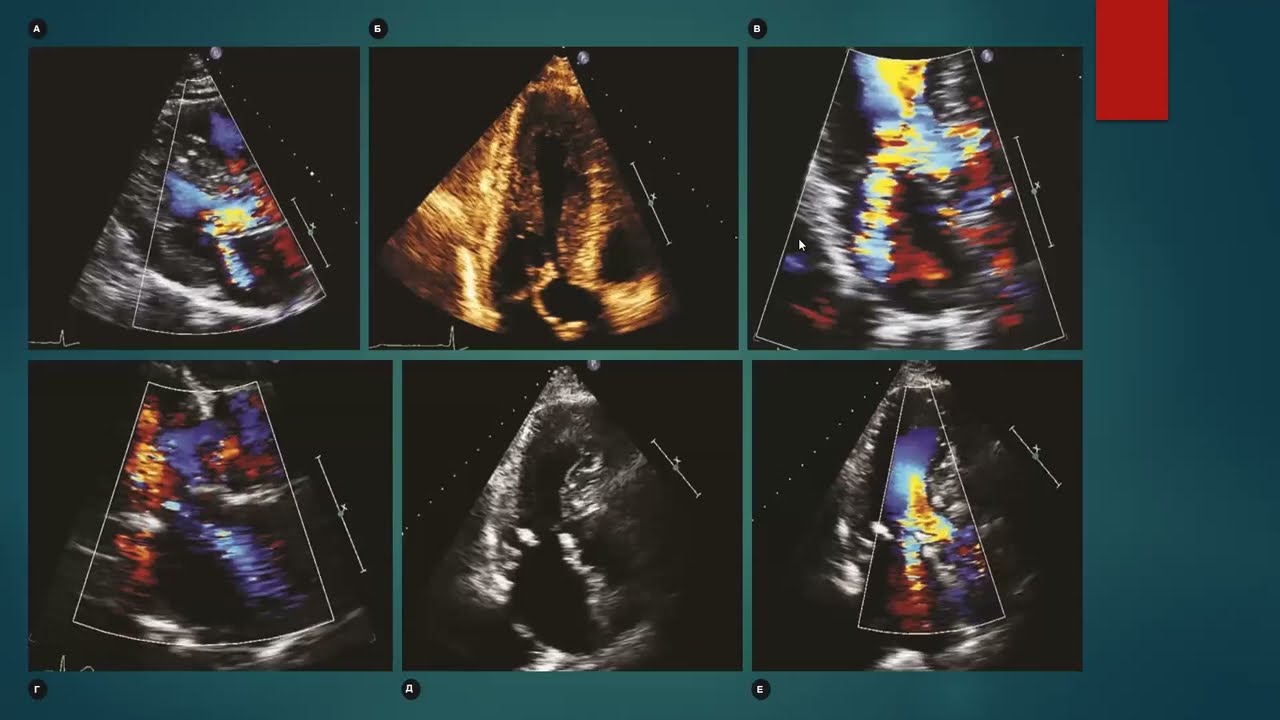

Уплотнение стенки левого желудочка

Уплотнение стенки левого желудочка 97 фото